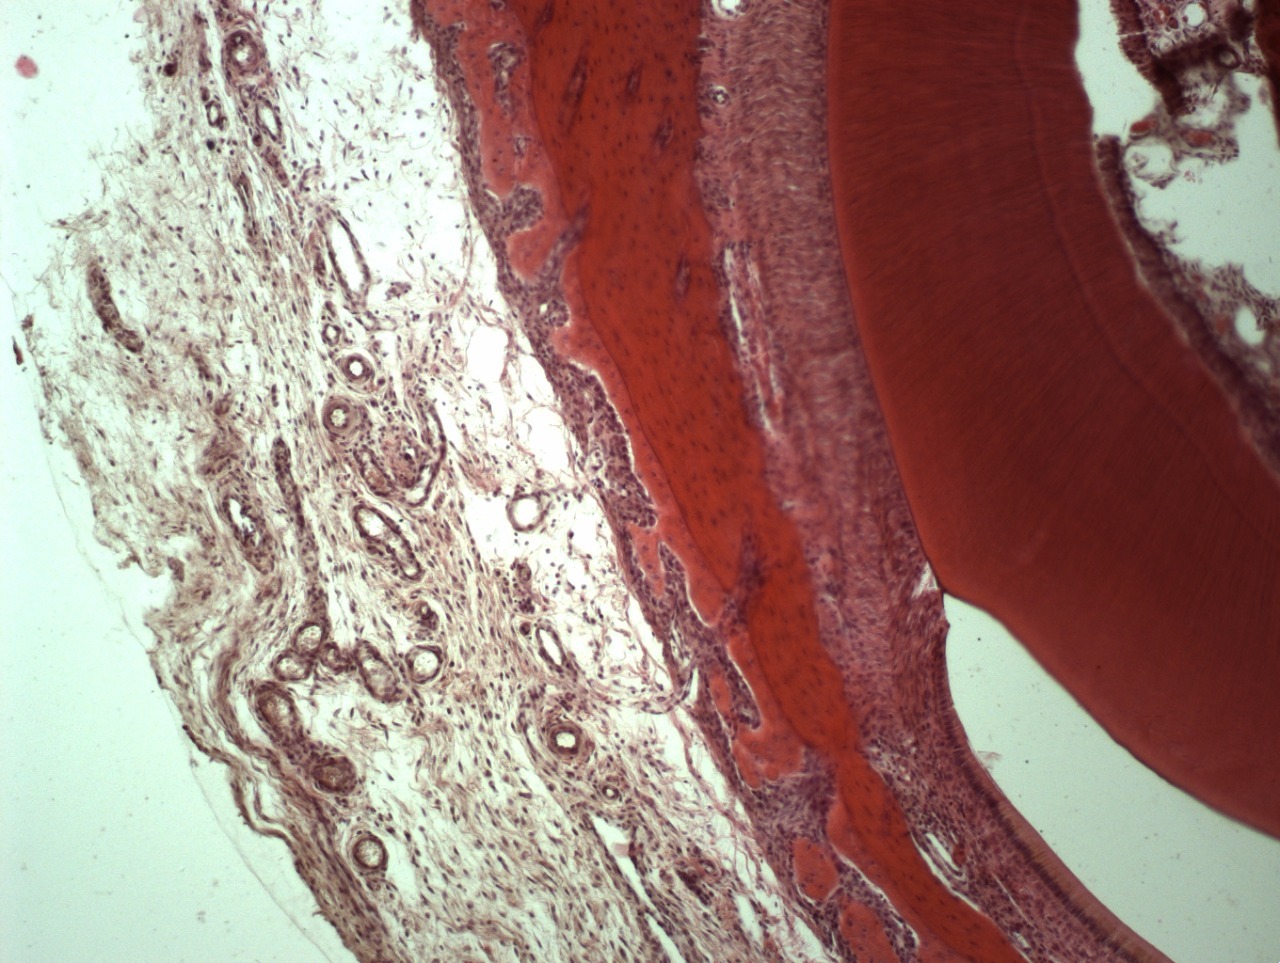

• Например, таким образом удаляются все следы жира, белка, нуклеиновых кислот, мертвых клеток и их компонентов, неколлагеновых белков и прочих соединений. Вследствие такой очистки остается только коллагено-минеральный каркас мертвого межклеточного вещества костной ткани, состав которого стабилен на протяжении всей жизни человека.

• Деминерализованную кость применяют дополнительно для восстановления внутренних костных дефектов: через нее лучше растут кровеносные сосуды, так как она содержит морфогенетический белок (МГБ), но за счет отсутствия минерального каркаса не способна удержать трехмерный объем.